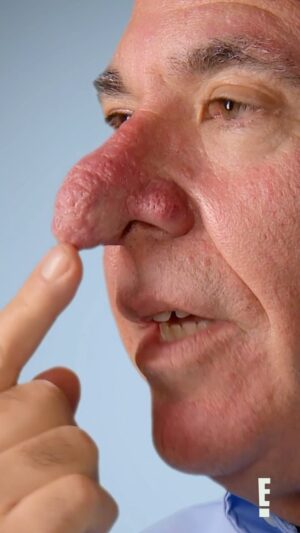

12.4K Likes – Paul Nassif Instagram

Caption : In all of my years as a facial plastic surgeon, I have NEVER seen a rhinophyma case like this! 🤯 You can’t miss what happens on an all-new #Botched tonight at 10/9c on @eentertainment! 💜 🔊 Sound: On! @botchedtv #rhinophyma #rhinoplasty #rhinoplastyspecialist #transformation #tv #tvshow #newepisode #plasticsurgery #botchedplasticsurgeryLikes : 12424